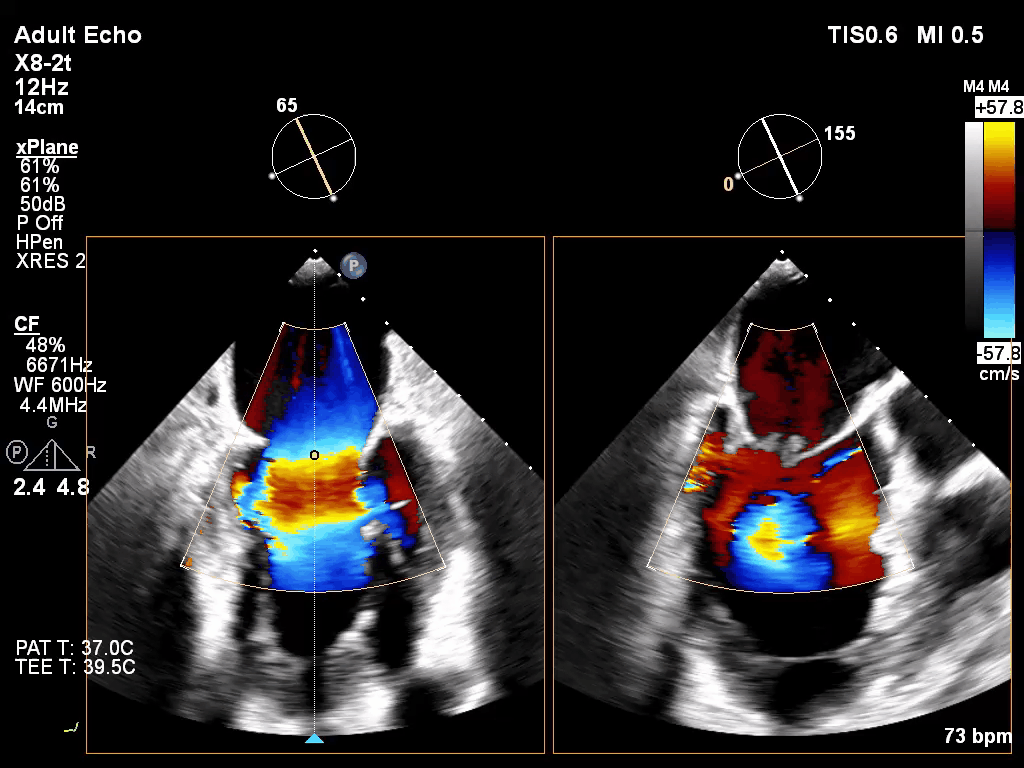

经食道超声心动图(TEE)提示:二尖瓣病变Carpentier II型,DMR,二尖瓣2区反流及P2腱索断裂并瓣叶脱垂,Gap 6 mm,Width 15 mm, 瓣口面积6.7 cm²,2区前叶长20 mm,后叶长19 mm。MR4+,反流束来自于2区,偏心性反流束,指向前叶;VC 11 mm。房间隔穿刺空间约4.5 cm。

术前TEE XPLANE

术前TEE XPLANE COLOR

经术前积极抗心衰等治疗,心功能较前改善。术前准备妥后手术于全麻下进行,经右侧股静脉--房间隔途径,4Ch切面确认穿刺高度满意,穿刺房间隔后交换置入Superstiff至左上肺静脉,之后置入导引鞘及夹合器输送系统,在TEE引导下,将2枚G12P型号的夹合器顺利植入到二尖瓣A2/P2区,确定夹合器位置稳定。彩色多普勒超声提示:二尖瓣微量反流,MG 2 mmHg,肺静脉多普勒波形由反向恢复正常,左房压显著下降。多切面证实夹合组织充分后释放,撤除器械输送系统后右侧腹股沟皮肤穿刺口加压包扎,术毕。手术室内超快通道拔除气管插管后送ICU监护。